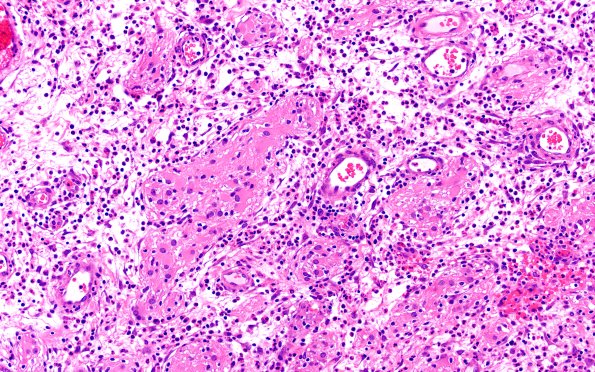

6B6 Nasal glioma (Case 6) H&E 20X

6B6,7 Islands of reactive glial cells are surrounded by PMNs. (H&E)